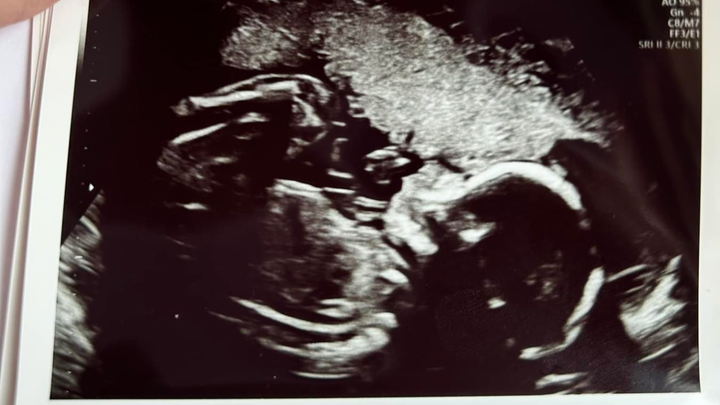

Hi my name is Todd Dudley and my wife Alexis and I are setting this up to help with expenses when our daughter is born late September. Our daughter Rosalie has been diagnosed with a congenital heart defect called transposition of the greater arteries which means the two major arteries of her heart are switched and because of this she will not be able to oxygenate her body when she is born and will need open heart surgery within a few days after birth. This surgery will require the surgeon to go in and switch these two arteries and reattach them to the correct sides of the heart. They also have to move the coronary arteries as well which is the tricky part. Anything would help us with living expenses, travel, food, and medical bills associated with her having to stay in UVA NICU and Cardiac ICU for 3 weeks to a month. My wife will be staying up there the whole time and I’ll have to travel back and forth and take care of our 20 month old. We really appreciate any help so we don’t have to stress about bills while we are already extremely worried for our daughter and her recovery. If you can’t donate we ask for continued prayers for a successful surgery and speedy recovery. God bless!